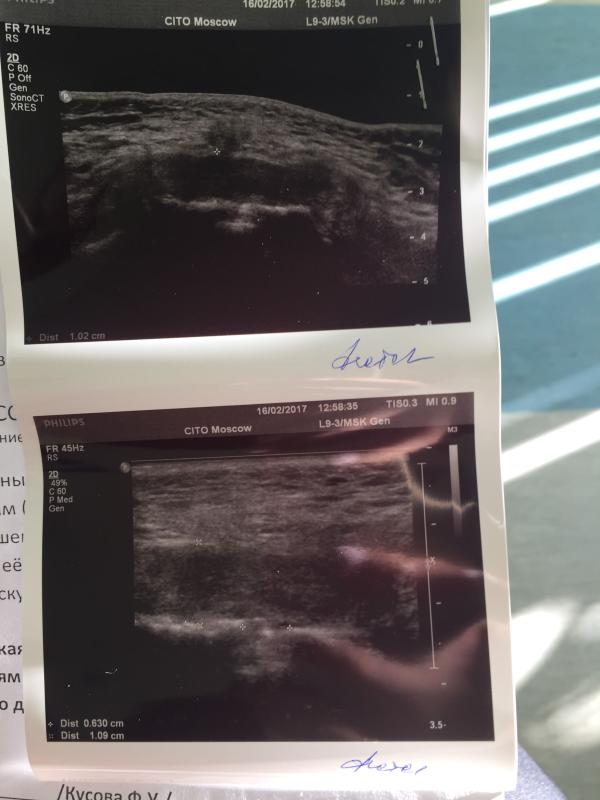

Примерно на 34-35 неделе меня начали накрывать все прелести симфизита, о котором при первой Б я даже не слышала: не могла без слез перевернутся, встать без помощи и быстро подойти к ребёнку. С каждым днём боль становилось терпеть все труднее и после планового осмотра у своей гини меня отправили в ЦИТО к орпопеду на ул. Приорова. Сама консультация у врача бесплатная (для жителей Москвы и МО✅), а вот за 3 минуты УЗИ пришлось заплатить 1020❗️(сумма небольшая, но все же неожиданно). Дали заключение, что расхождением симфиза ~6мм (норма). Ортопед рекомендовал бандаж на весь оставшийся срок и на 3 неделе после родов+ ЭА при родах. Сейчас мечтаю уже поскорее родить, чтобы все побыстрее встало на свои места 😞